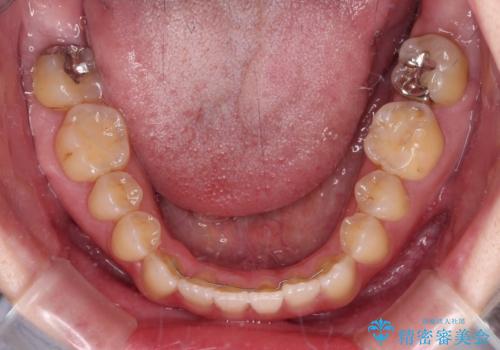

オープンバイトと前歯のデコボコをインビザライン矯正で解消

- 前歯の開咬を気にして来院された患者様です。

開咬の治療は、前歯を閉じるように動かすとともに、上下臼歯を圧下(骨内にめり込ませる)させることで進めて行きます。

インビザラインは臼歯の圧下を効果的に行えるため、インビザラインを用いて矯正治療を行うこととしました。

オープンバイトは舌の突出癖により誘発され、治療後も突出癖が残っている容易に後戻りしてしまいます。

治療期間を短縮するためにも、舌突出癖の改善が極めて重要となります。